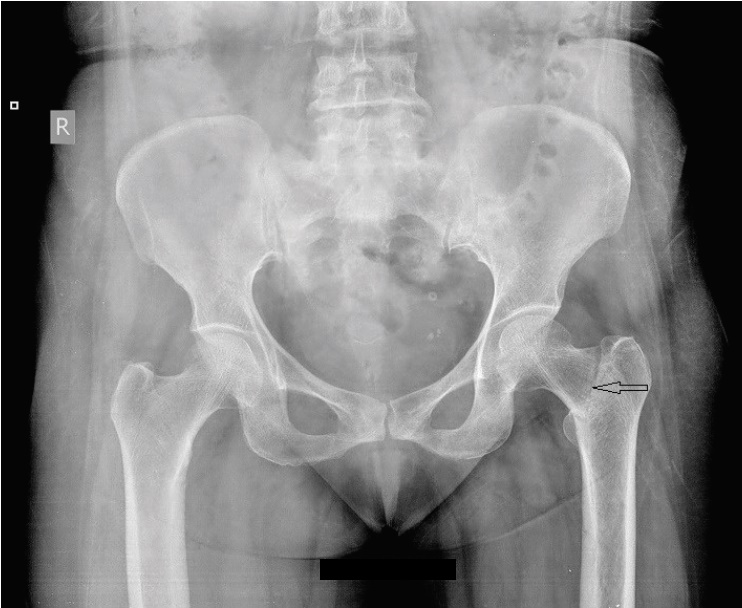

Radiological studies showed bilateral tibial shaft fractures, multiple fractures in bilateral tarsals (Figures 1 to 3). A PET Scan showed multiple insufficiency fractures of bilateral tibia, neck of right femur, metacarpal bones and scapula (Figures 4 to 7).

Figure 3.X-ray showing neck femure fracture on left side.